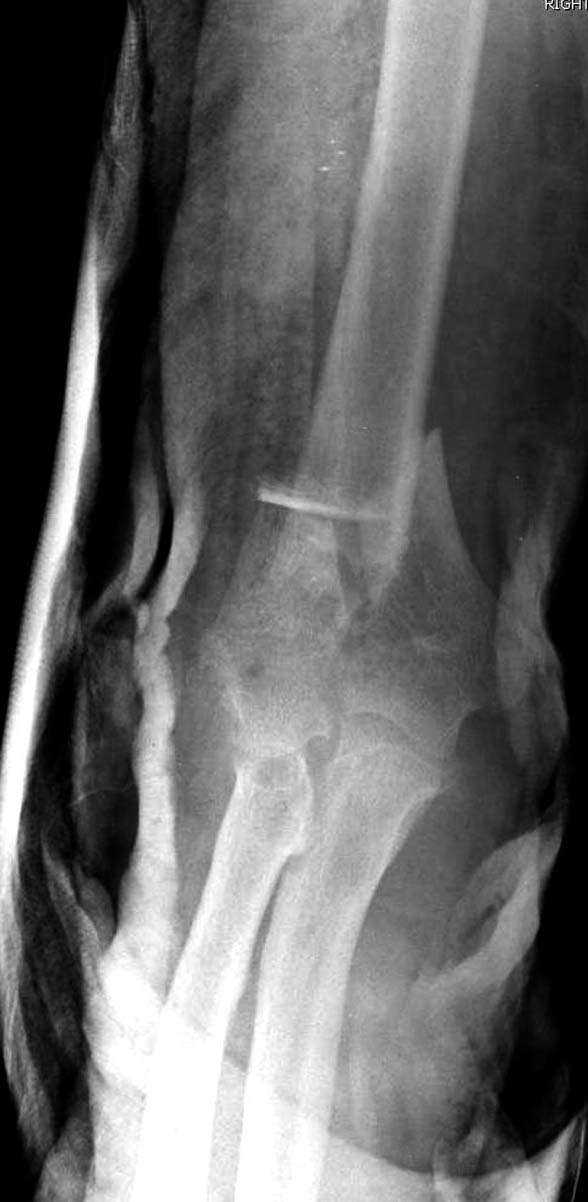

Здесь открытый перелом, временный наружный фиксатор и окончательная фиксация пластинами. Второй случай фиксация без остеотомии отростка пластинами Biomet-DePuy...